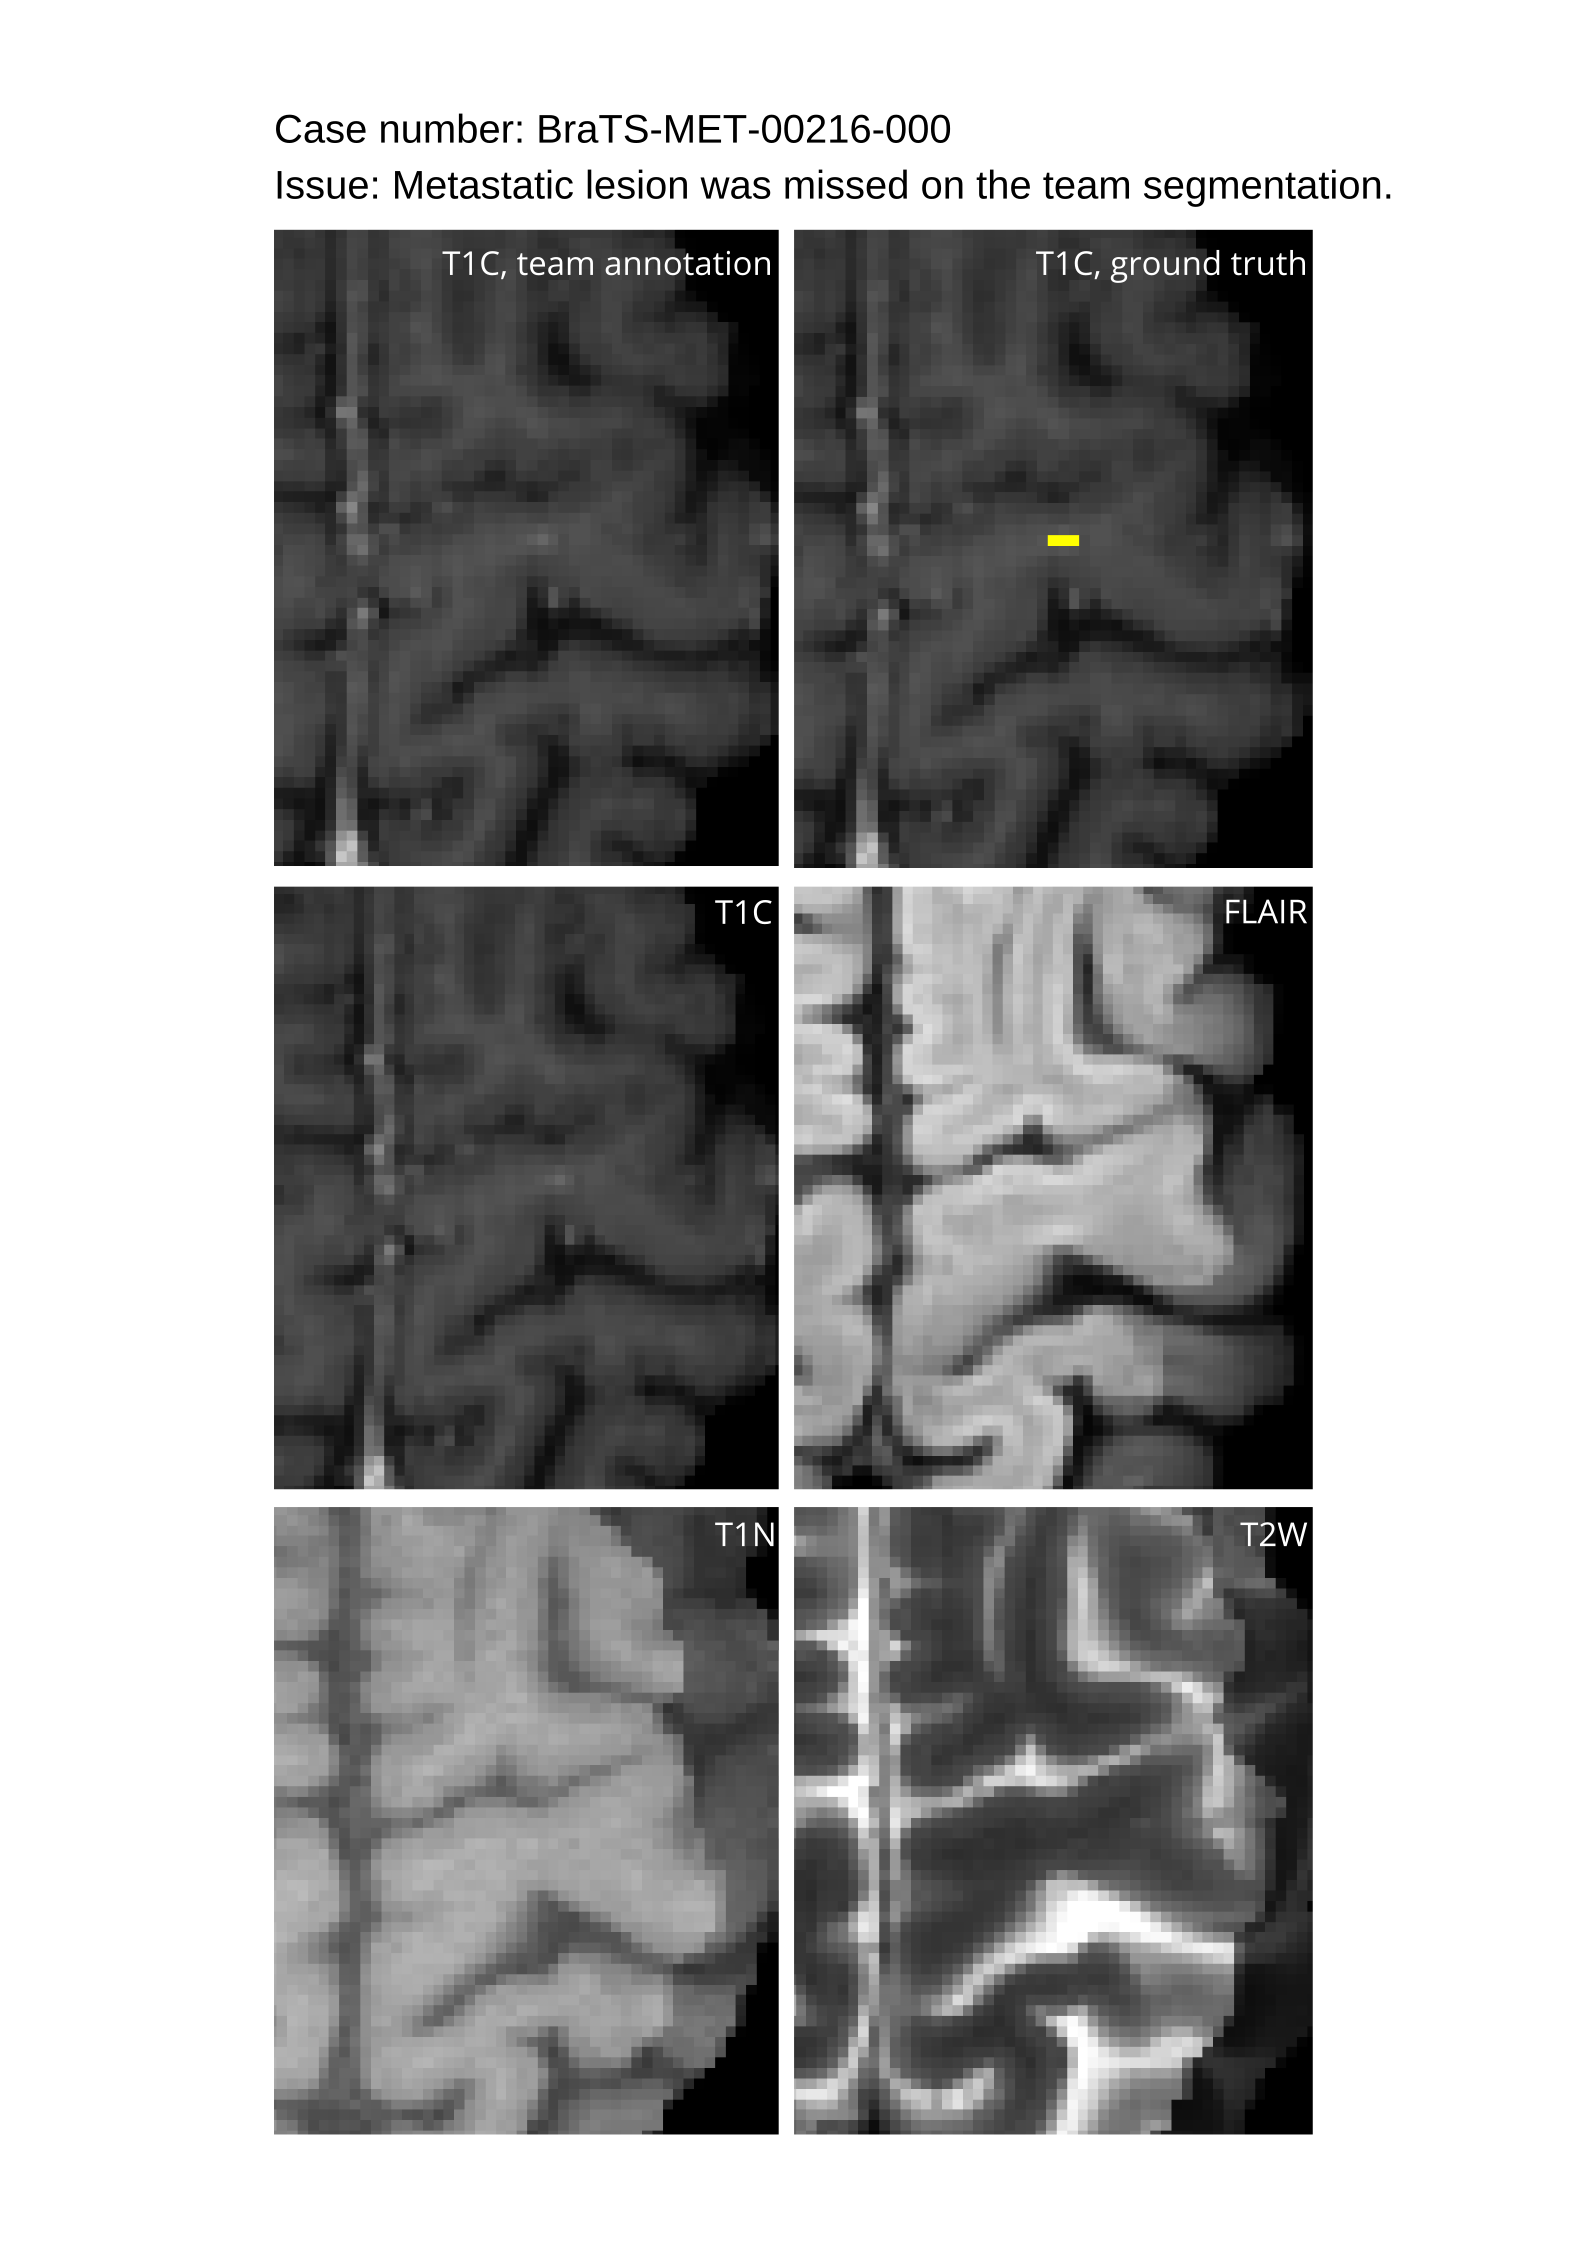

4.9 Common Errors of Automated Segmentations

Based on observations from previous BraTS challenges, common errors in automated segmentations were identified. The most typical errors in the current challenge included:

1. 1.

Automated algorithms missing small metastases. Enhancing metastasis was fused using the minority voting algorithm to aggregate all enhancing tumor voxels identified by the three algorithms. However, many small metastases were missed and were manually segmented by neuroradiology attendings.

2. 2.

Segmentation of white matter changes from microvascular disease. Peritumoral edema segmentations were checked by neuroradiology attendings and modified.

3. 3.

The segmentation of non-enhancing lesions that have intrinsic T1 hyperintensity. Voxels with intrinsic T1 hyperintensity were manually removed from ET segmentations.

These insights led to specific adjustments in the annotation process to enhance accuracy.